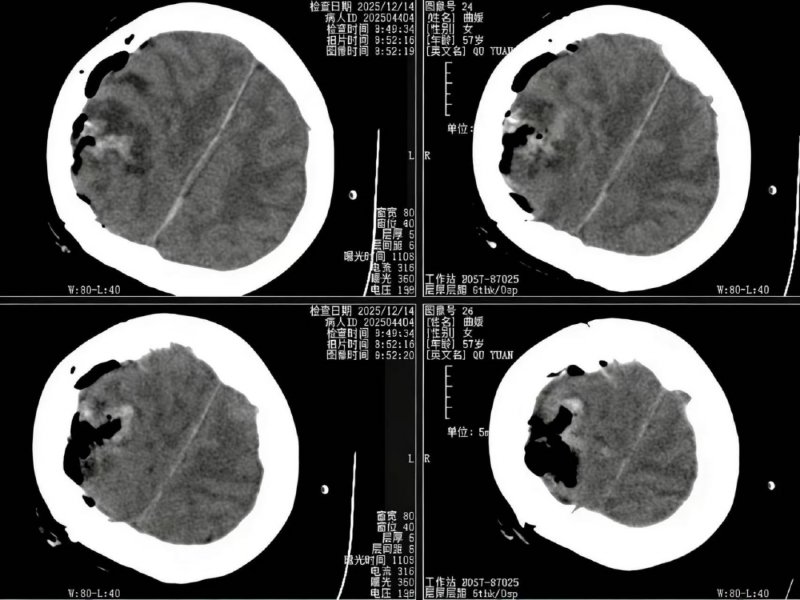

术后复查CT提示肿瘤全切,患者无新增神经功能障碍。病理结果为WHOⅠ级良性脑膜瘤,患者已顺利康复出院。